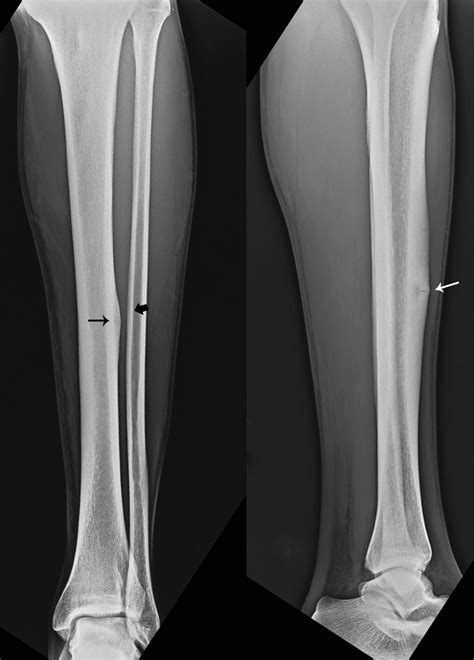

The symptoms of a stress fracture of the shin can vary, but they often include pain, swelling, and bruising in the affected area. The pain may be dull and aching at first, but it can become sharper and more severe over time. In some cases, the pain may be severe enough to limit activity or cause significant discomfort. A thorough medical evaluation, including a physical examination and imaging studies, such as X-rays or magnetic resonance imaging (MRI), is typically necessary to diagnose a stress fracture of the shin.

| X-rays | Imaging study that uses radiation to produce images of the bones. |

| Magnetic Resonance Imaging (MRI) | Imaging study that uses a strong magnetic field and radio waves to produce detailed images of the bones and soft tissues. |

| Bone Scan | Imaging study that uses a small amount of radioactive material to produce images of the bones. |

| Computed Tomography (CT) Scan | Imaging study that uses X-rays and computer technology to produce detailed images of the bones and soft tissues. |